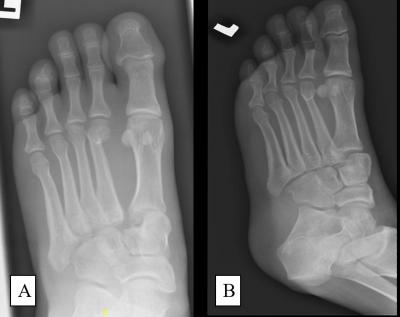

Figure 1: (A) Anteroposterior view and (B) oblique view of left foot plain radiograph showing Lisfranc injury of the left foot